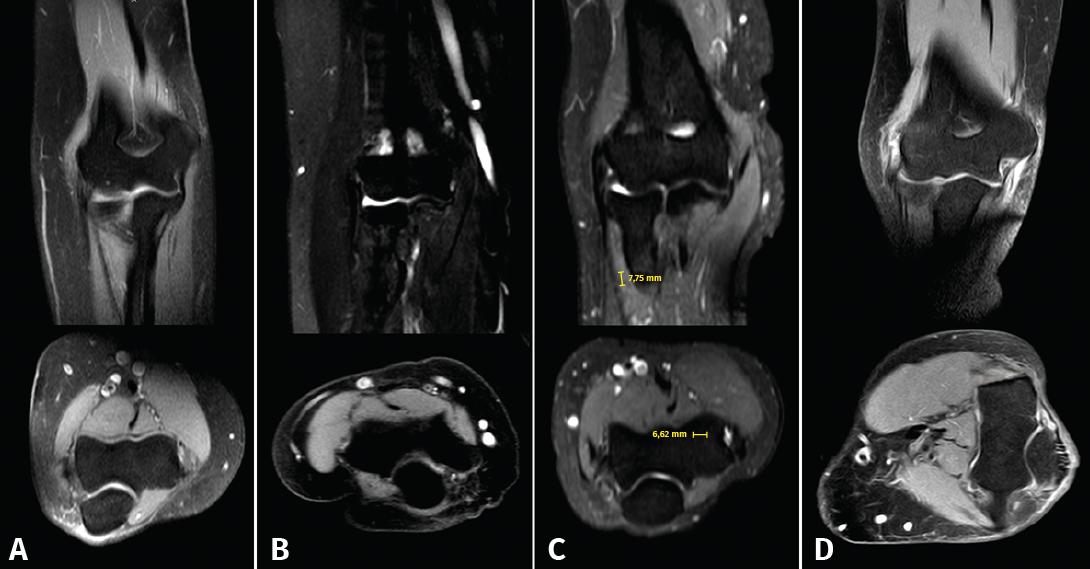

Estos autores proponen un sistema de gradación según los hallazgos en la RM, tanto del grado de tendinosis como del grado de retracción del tendón desinsertado del epicóndilo (Figura 9):

Figura 9. Imágenes de resonancia magnética que ilustran los grados de afectación tisular de la clasificación de Walton. Se pueden apreciar cortes coronales y axiales de tendinopatía del espesor del tendón sin rotura (A) y de los distintos grados de lesión con rotura de la inserción según su longitud de separación del epicóndilo; B: grado 1 (< 2 mm); C: grado 2 (2 a 5 mm); D: grado 3 (> 6 mm).

Según el grado de tendinosis:

- Grado 1. Normal-leve: baja intensidad de señal homogénea o pequeños focos de aumento de señal en el estudio de supresión grasa en T2.

- Grado 2. Moderada: aumento de señal moderado en T2.

- Grado 3. Severa: aumento de señal generalizado en el tendón en T2.

Según la longitud de separación de la rotura respecto al epicóndilo:

- Grado 1: 0-2 mm.

- Grado 2: 2-5 mm.

- Grado 3: > 6 mm.

Diversos estudios demuestran que la mayoría de los pacientes con diagnóstico de tendinopatía lateral crónica de codo presentan alteraciones de señal en imágenes de RM(23,24). Sin embargo, aunque estos hallazgos en RM sí parecen estar correlacionados con las alteraciones histológicas, la correlación entre el grado de alteración de la señal radiológica y la intensidad de los síntomas clínicos no está completamente establecida(25,26).